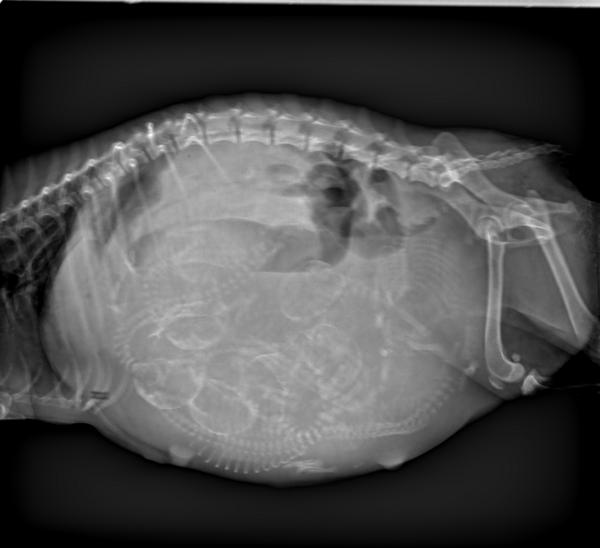

DR显示

6个胎儿胎位不正后脚朝下

编辑

初步诊断

狗狗同时两个胎泡流出,

DR显示有可能两个胎儿堵在阴道上端,

建议家长为狗狗选择剖腹产手术。